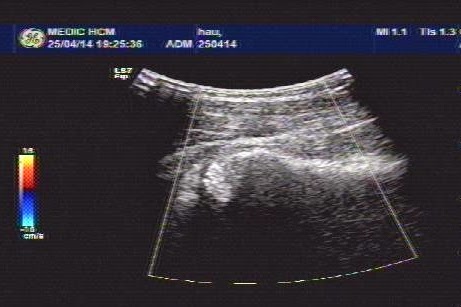

Upon ultrasound the right hip joint showed widering of the hip joint space with fluid collection, and abnormal echostructure of the head of femoral bone (see 3 ultrasound pictures at right hip).

Ultrasound examination of the right hip report was abnormal in suggesting arthrosis of right hip joint).